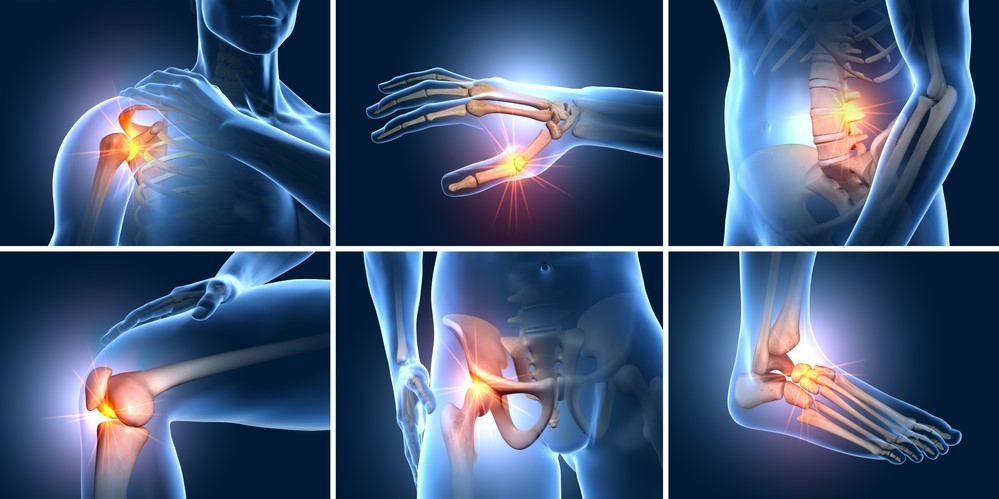

Thoái hóa khớp là dạng viêm khớp phổ biến ảnh hưởng đến hàng triệu người trên toàn thế giới. Trình trạng này xảy ra khi lớp sụn bảo vệ đệm các đầu xương của bị hư hại, tổn thương. Nếu không được điều trị kịp thời có thể dẫn đến nguy cơ tàn tật cho người bệnh.

Khớp gối: là một trong những khớp chủ chốt của hệ xương khớp, vừa là “trạm điều khiển” cử động của cẳng chân và bàn chân vừa nâng đỡ toàn bộ trọng lượng cơ thể. Vai trò càng lớn rủi ro càng cao, dễ khiến khớp gối bị chấn thương khi khuân vác các vật nặng, chơi thể thao như bóng đá, điền kinh…

Cột sống thắt lưng: trực tiếp thực hiện các chuyển động cúi, xoay hông và uốn cong lưng, đồng thời phải nâng đỡ phần trên của cơ thể. Chính vì phạm vi hoạt động rộng và chịu áp lực cao nên cột sống thắt lưng dễ gặp phải các tình trạng như đau nhức, thoái hóa, gai cột sống, thoát vị đĩa đệm…

Khớp vai: đau mỏi khớp vai là tình trạng phổ biến của dân văn phòng phải ngồi lâu trước máy tính, người nằm ngủ sai tư thế, công nhân khuân vác, vận động viên các bộ môn như tennis, cầu lông, bóng rổ… Ngoài tác động cơ học, khớp vai bị đau mỏi còn do thoát vị đĩa đệm cột sống cổ hoặc gai xương đốt sống cổ chèn ép lên dây thần kinh.

Khớp ngón tay: tham gia vào hầu hết các công việc thường ngày, bao gồm: xách đồ vật, nấu ăn, giặt giũ… Chúng phải cử động lặp đi lặp lại như: gõ máy tính, cắt tóc, sơn tường… hoặc chơi một số bộ môn bóng bàn, bóng rổ, tennis… Cấu trúc nhỏ nhưng phải đảm nhiệm nhiều hoạt động khác nhau, căng thẳng dồn nén ngày qua ngày, làm khởi phát cơn đau ở các khớp ngón tay.

Đau nhức không chỉ là cảm giác mà còn là tín hiệu cảnh báo những vấn đề xương khớp nghiêm trọng. Nếu cơn đau xuất hiện liên tục với mức độ tăng dần có thể dẫn đến bệnh viêm khớp, thoái hóa khớp. Các bệnh lý này làm suy giảm chất lượng dịch khớp, bào mòn sụn và xương dưới sụn, hình thành gai xương hoặc thoát vị đĩa đệm. Đây là lý do khiến khớp gối, cột sống thắt lưng, khớp vai và khớp ngón tay đau nhức mãi không dứt.